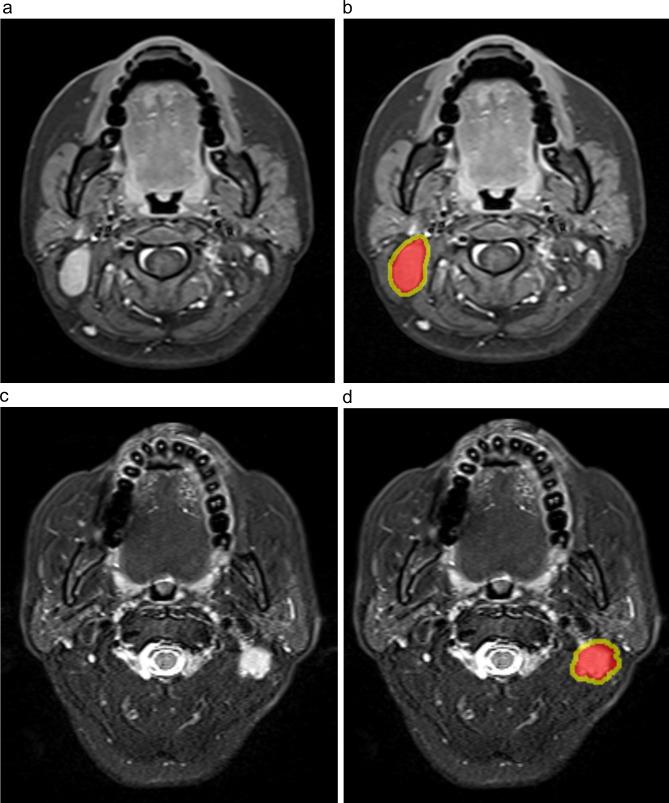

To establish and validate radiomic models combining intratumoral (Intra) and peritumoral (Peri) features obtained from pretreatment MRI for the prediction of treatment response of lymph node metastasis from nasopharyngeal cancer (NPC).

METHODS

One hundred forty-five NPC patients (102 in the training and 43 in the validation set) were retrospectively enrolled. Radiomic features were extracted from Intra and Peri regions on the metastatic cervical lymph node, and selected with the least absolute shrinkage and selection operator (LASSO). Multivariate logistic regression analysis was applied to build radiomic models. Sensitivity, specificity, accuracy, and the area under the curve (AUC) of receiver operating characteristics were employed to evaluate the predictive power of each model.